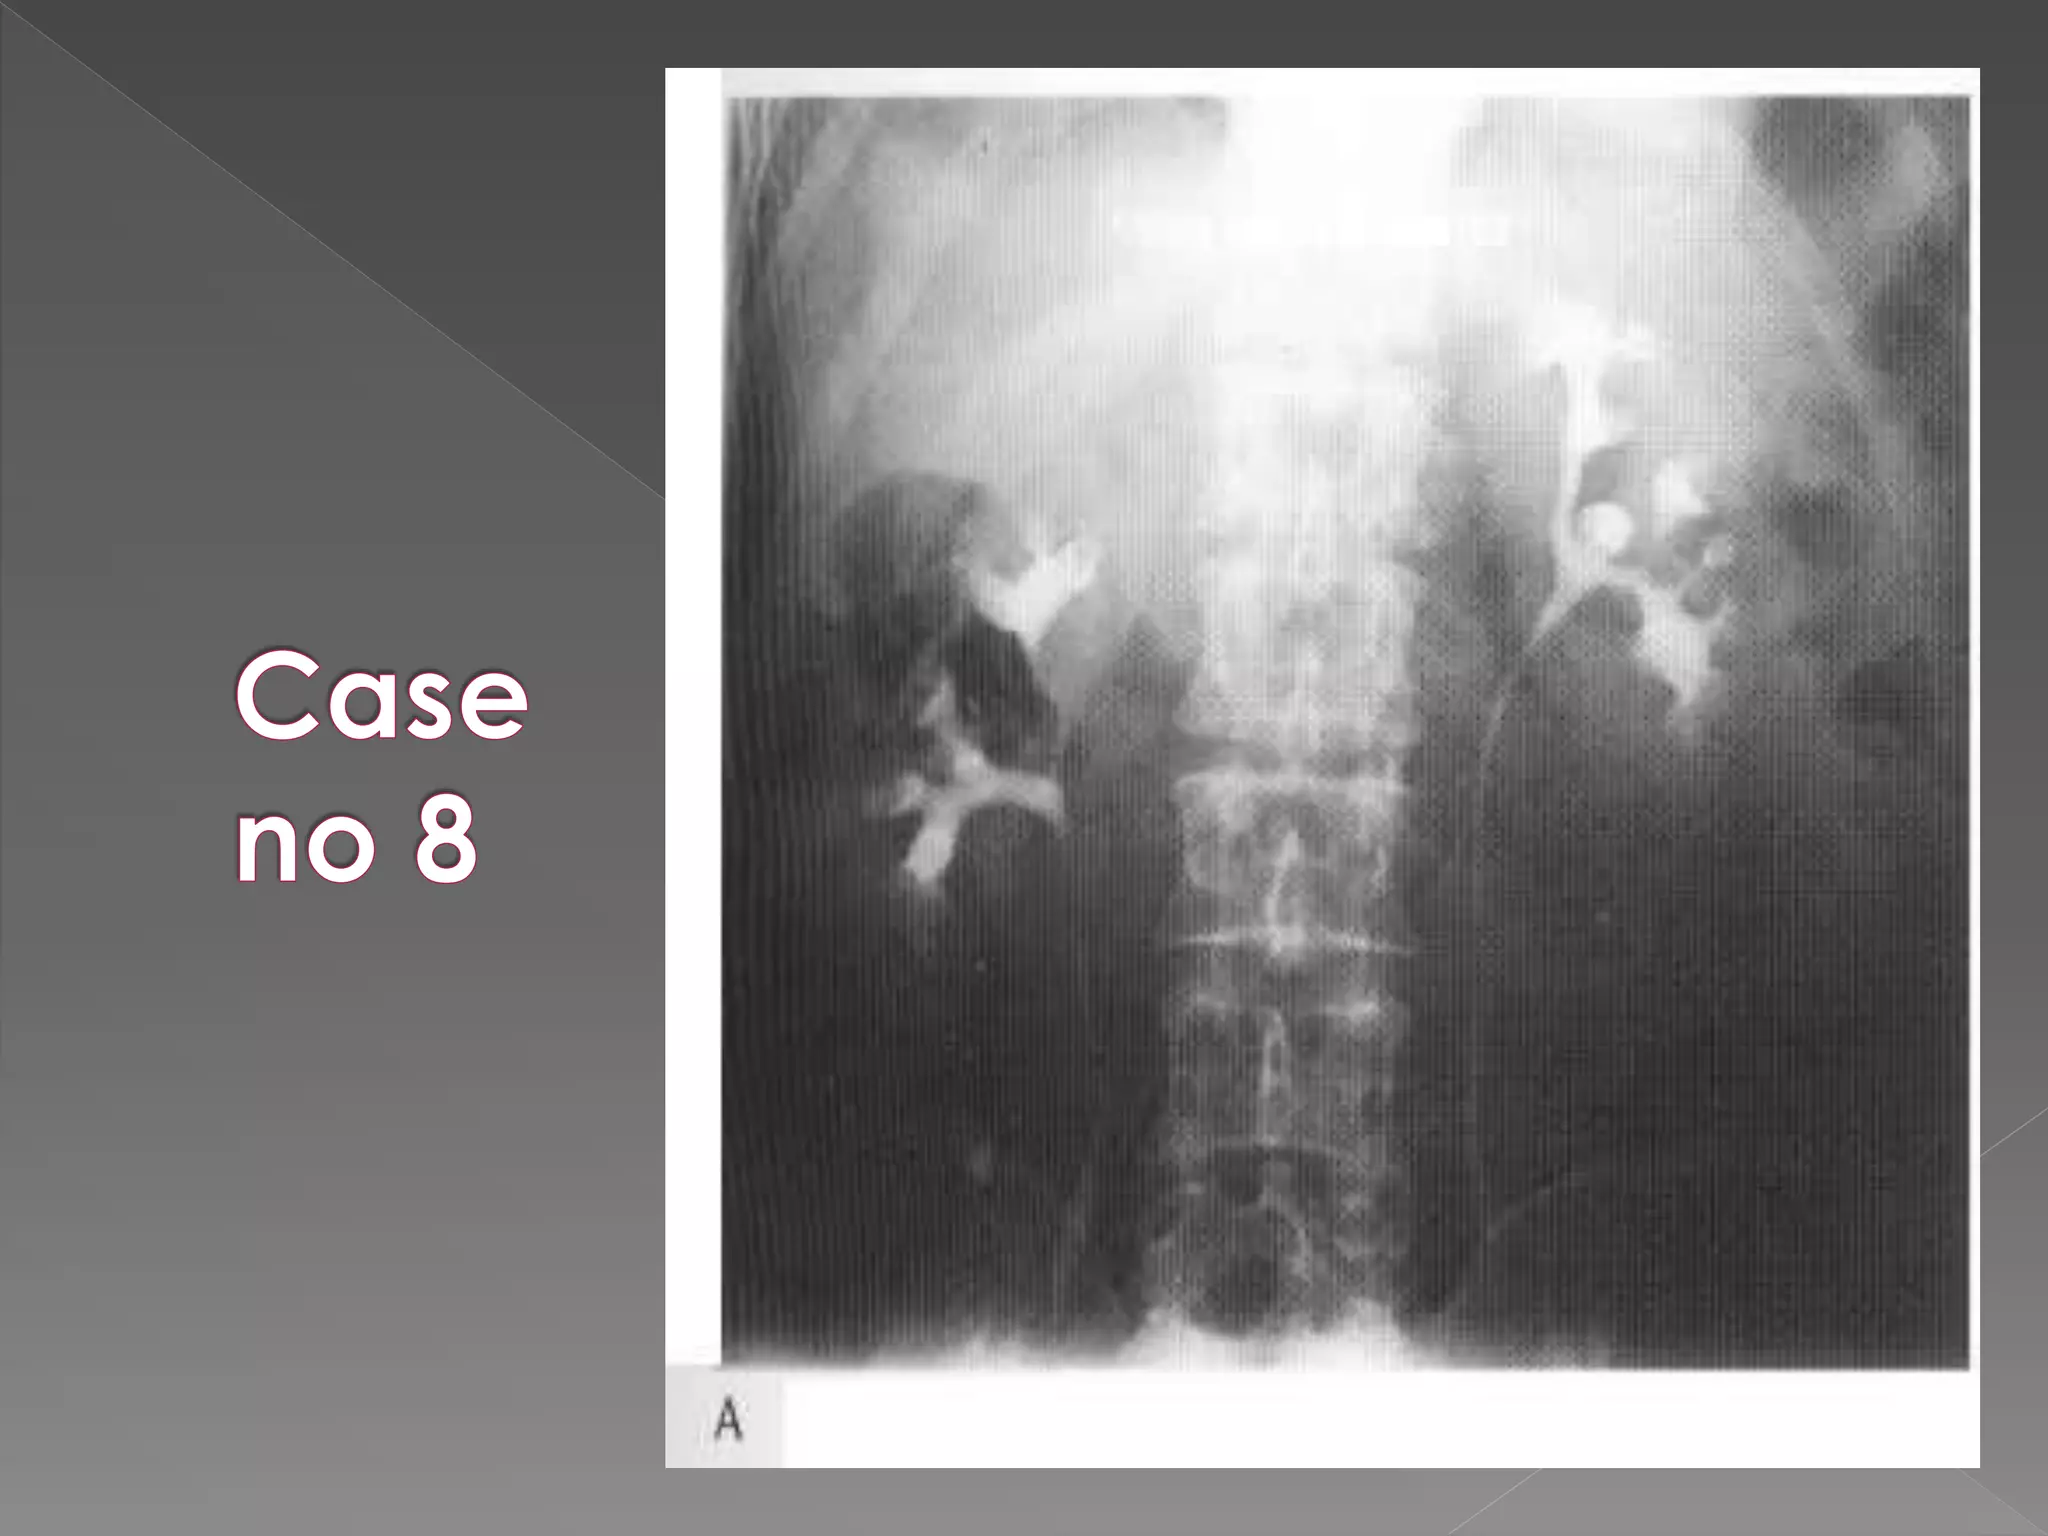

 The plain film demonstrates

calcification within distended

upper pole calyces

 The plainfilm demonstrates calcification within distended upper pole calyces